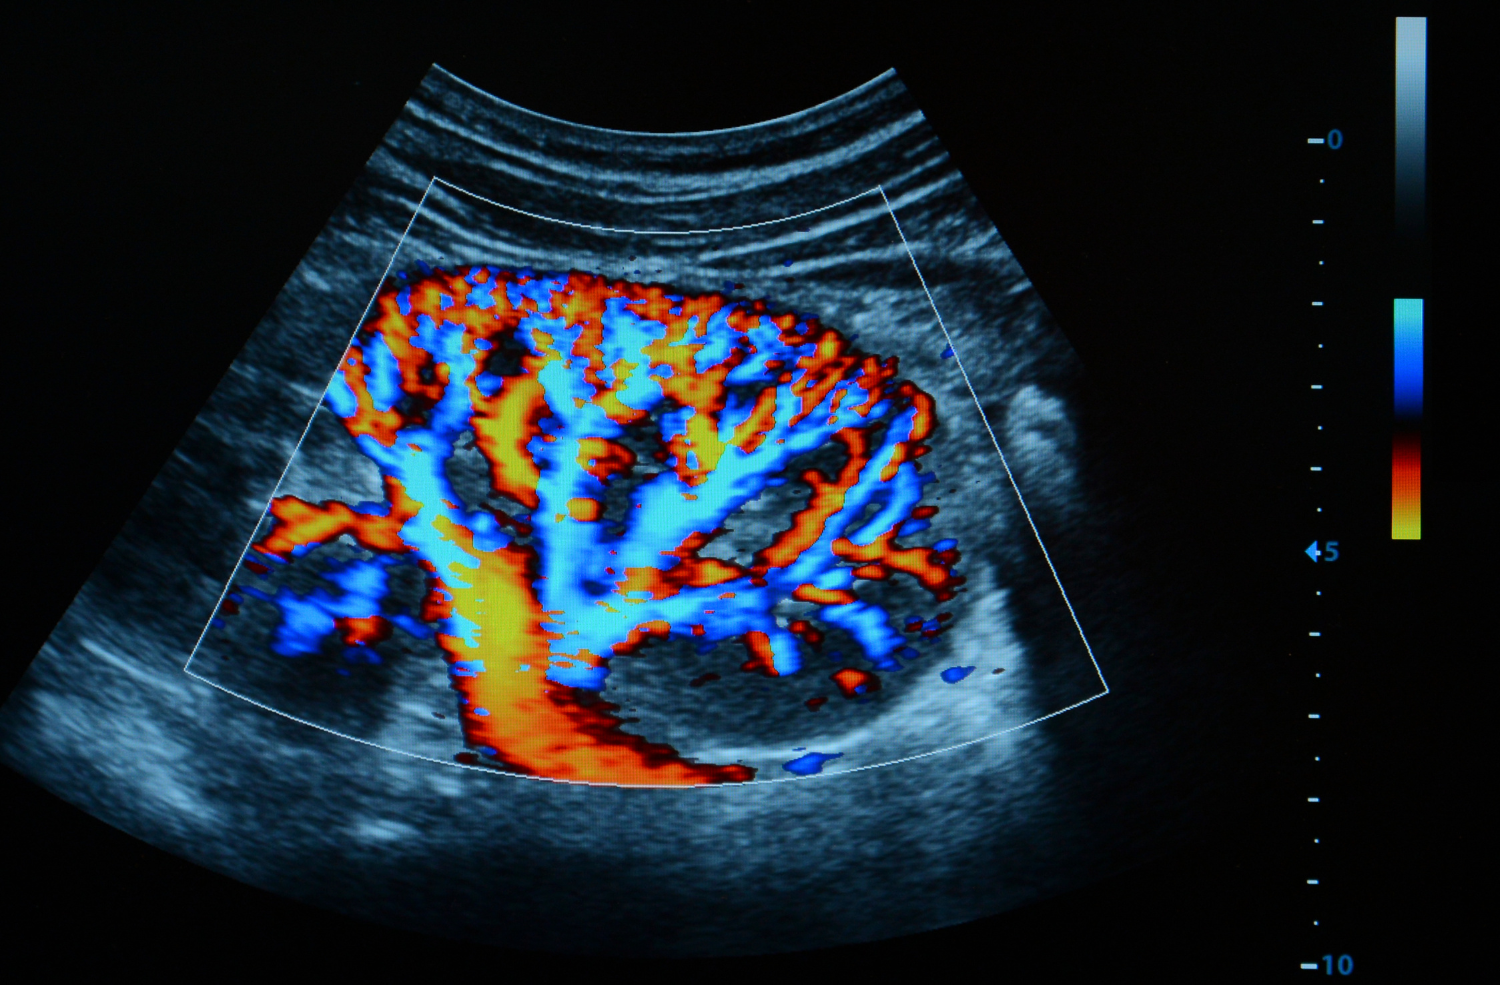

L’ecocolordoppler (spesso chiamato “ecodoppler”) è un esame non invasivo che, tramite ultrasuoni, permette di valutare vasi sanguigni e flusso di sangue (arterie e vene). È uno strumento fondamentale per controllare lo stato della circolazione e individuare eventuali alterazioni in modo accurato.

L’ecocolordoppler viene eseguito in ambulatorio: lo specialista utilizza una sonda sulla cute con un gel, osservando in tempo reale morfologia del vaso e direzione/velocità del flusso.